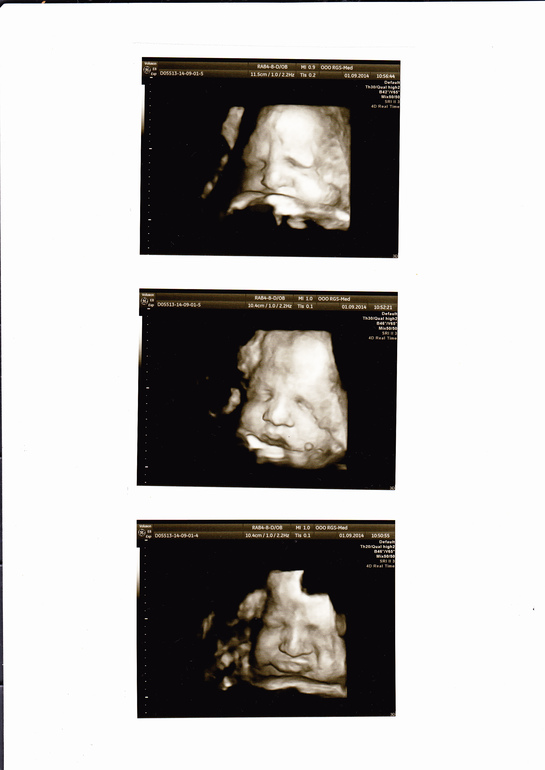

34,6 недель,финишная прямая не за горами))3Д УЗИ+фото)))

Сегодня у нас срок 34,6 неделек,завтра будет 35 и останется буквально 3-4 недели до счастья в ладошках)))Мальчишка растет у меня длинноногий(весь в папу)стопа уже 6,8см!!!Большие будут ножки...)))Воды в норме,индекс 15.Плацента 2 степени зрелости.Есть однократное обвитие,но это ничего страшного,все равно КС будут делать)))Приблизительный вес 2652гр,так что совсем не слоненок у меня,а в меру упитанный мужчинка

.Щеки конечно хорошие накушал)))Сначала сынок еще раз продемонстрировал свою принадлежность к мужскому полу,и как обычно во весь экран-ну вообще не стесняется и не прячется))))А когда делали фото,так он в конце сделал такое уморительное личико:выпятил нижнюю губу,как -будто обиделся,и как мы его не уговаривали,все таки так и не повернул головушку,чтоб сделать красивую фотографию(((Но я рада и тем,которые у нас получились,тем более есть еще и видео)))